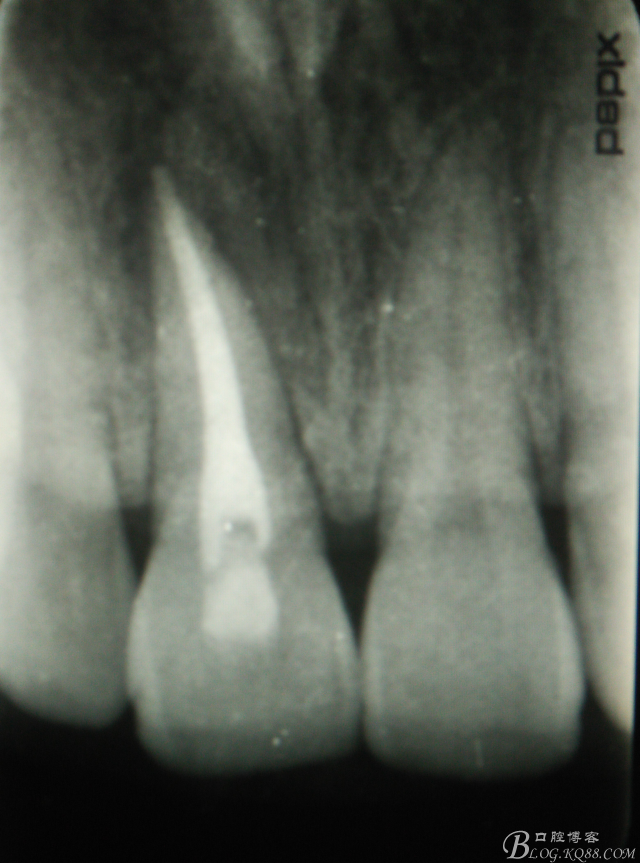

圖3.術(shù)前的11根尖片影像檢查:根充有點超填,根尖陰影明顯。范圍看著不大。